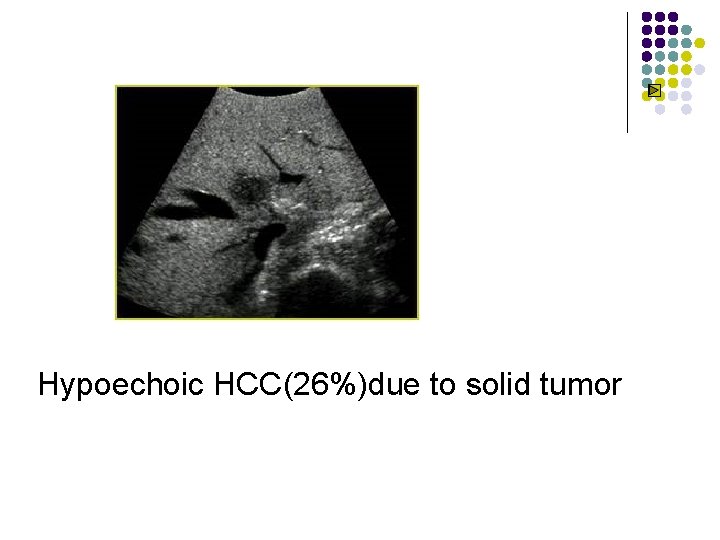

Sonographic Features of HCC l l l 86 -99% sensitivity; 90 -93% specificity; 65 -94% accuracy; Hyperechoic HCC(13%)due to fatty metamophosis or marked dilatation of sinusoids Hypoechoic HCC(26%)due to solid tumor HCC of mixed echogenicity (61%)due to nonliquefactive tumor necrosis

Hypoechoic HCC(26%)due to solid tumor